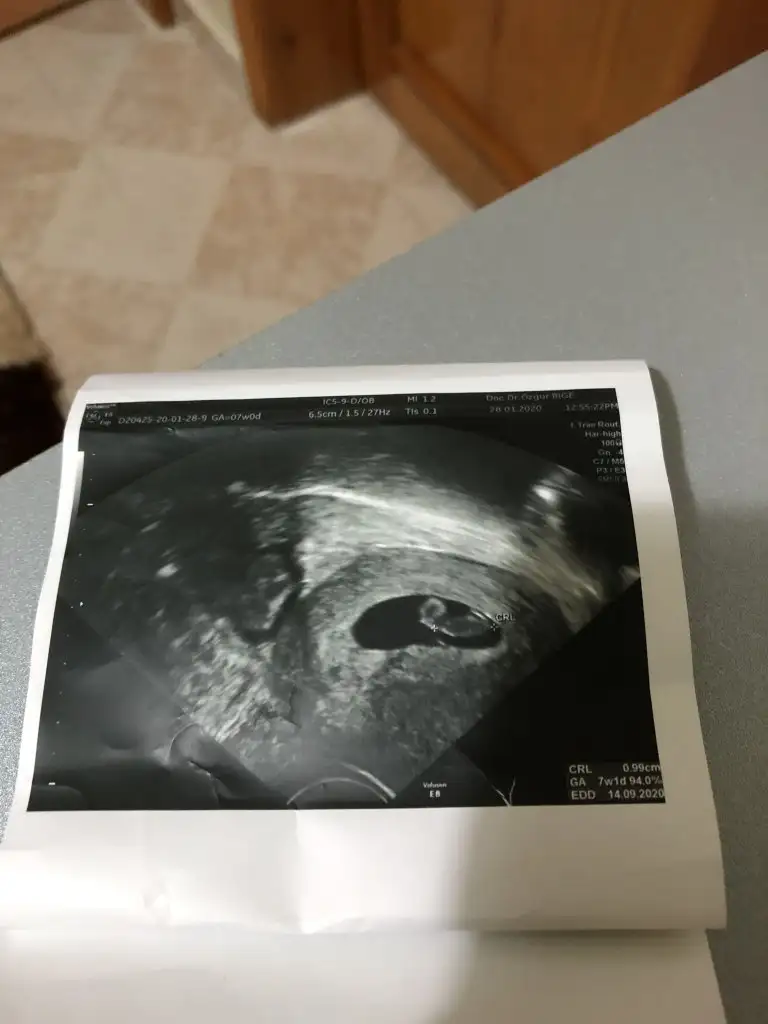

Buna göre erkek siz nub için 11 yada 12 hafta usg paylaşınMerhabalar 7+1 günlük alttan ultrason tahmin alabilirmiyim.

Teşekkür ederim cevabınız için 11 12 haftada da atarım bu dünkü ultrasonumuzdu.Buna göre erkek siz nub için 11 yada 12 hafta usg paylaşın